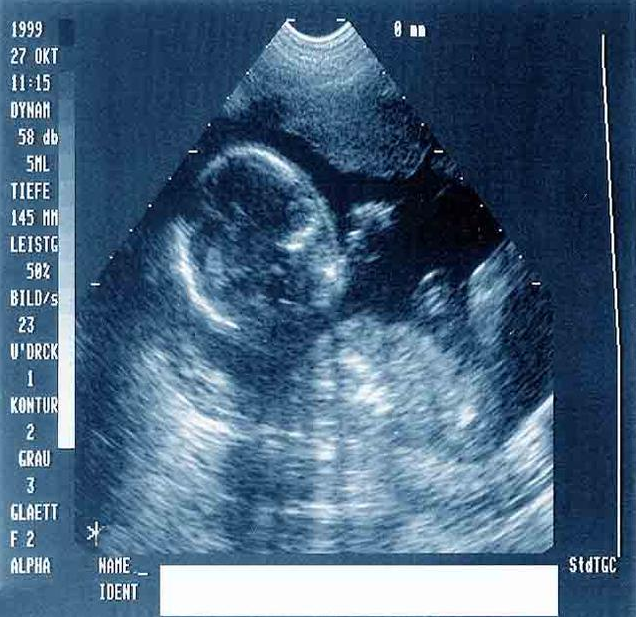

一般人的胚胎發(fā)育,30—40天形成的是胎囊,40—50天形成的是胎芽, 50—60天胎芽形成胎心。胎心就是胎兒的心跳,正常胎兒在八周心臟已形成,B型超聲可見心臟搏動(dòng)。如果B超聲像圖清晰顯示胚胎而無胎心搏動(dòng),常提示胚胎死亡及難免流產(chǎn),是胎停育的一種表現(xiàn)。